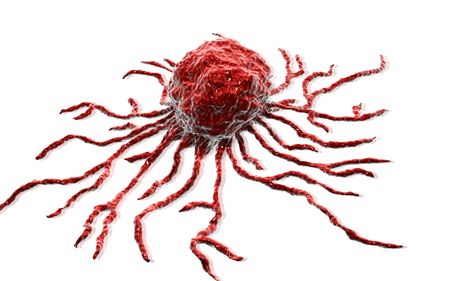

Cancer cell, malignant tumor cell

cancer cell or tumor illustration in high detail for medical concept 3d rendering

Cancer or tumor cell close-up 3D rendering illustration. Carcinoma, lymphoma, oncology, medicine, science, microbiology, cancerous pathology, health concepts.